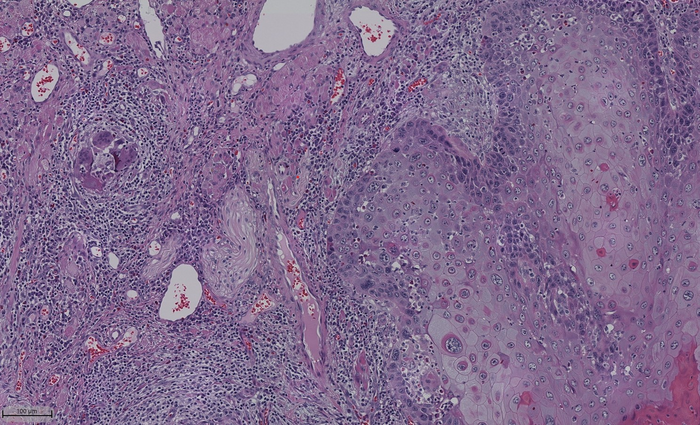

The team created a standardized metric for nerve density to clarify the variation in distribution of nerves in the oral cavity, called normalized nerve density, and showed its importance in tumor progression. Image Credit: Cindy Perez-Pacheco

The team looked at how the density of nerves within a tumor tied with the tumor's growth. The oral cavity has several regions, each with different functions. The way each area receives nerves is distinct; the nerves on the inside of the cheek have a different role and are fewer than nerves on the tongue. Given these variations, looking at the nerve density of the tumor without considering the normal innervation of the different areas in the oral cavity and each individual's variation to assess whether a tumor is aggressive leaves an inaccurate picture.

To account for this, the team created a standardized metric for nerve density to clarify the variation in the distribution of nerves in the oral cavity, called normalized nerve density and showed its importance in tumor progression. Most of the work was done with human tissue, and the team then validated the findings using a mouse model.

They used adjacent tissue to compare and determine a "normalized" density for different regions in the oral cavity. "We showed that tumors with high normalized nerve density seem to be associated with poor survival for patients with tongue cancer, which is the most common type of oral cancer," D'Silva explained. "We also found that patients with high normalized nerve density and a smaller distance between the nerve and the tumor have poorer outcomes."